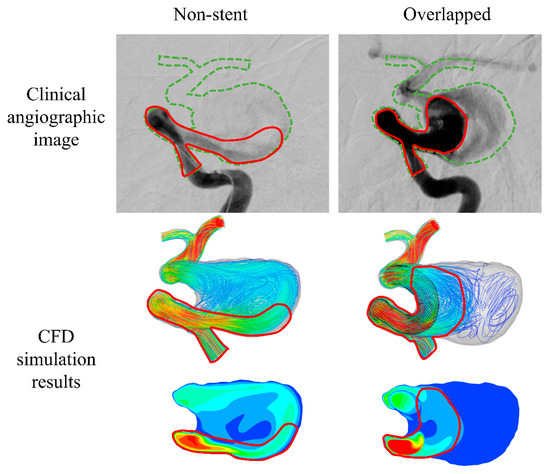

Search for PhD funding scholarships studentships in the UK Europe and around the world. CFD is capable of providing valuable hemodynamics which is useful in the clinical assessment of heart performance and the early diagnosis of heart dysfunction 3 6 7. The review then focuses on the applications of CFD in biomedical problems including cardiovascular diseases airflow pattern and aerosol deposition in lungs cerebrospinal fluid flow in brain and for artificial organ design analysis.

What does CFD stand for in Biomedical Engineering. CFD is the science of predicting fluid behaviour Flow field heat transfer mass transfer chemical reactions etc By solving the governing equations of fluid flow using a numerical approach computer based simulation The results of CFD analyses Represent valid engineering data that may be used for. Structured multi-block grid for an unruptured aneurysm in a cerebral artery a test case used in CFD Rupture Challenge 2013.